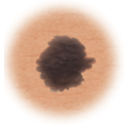

Normal mole.

This is a normal mole.